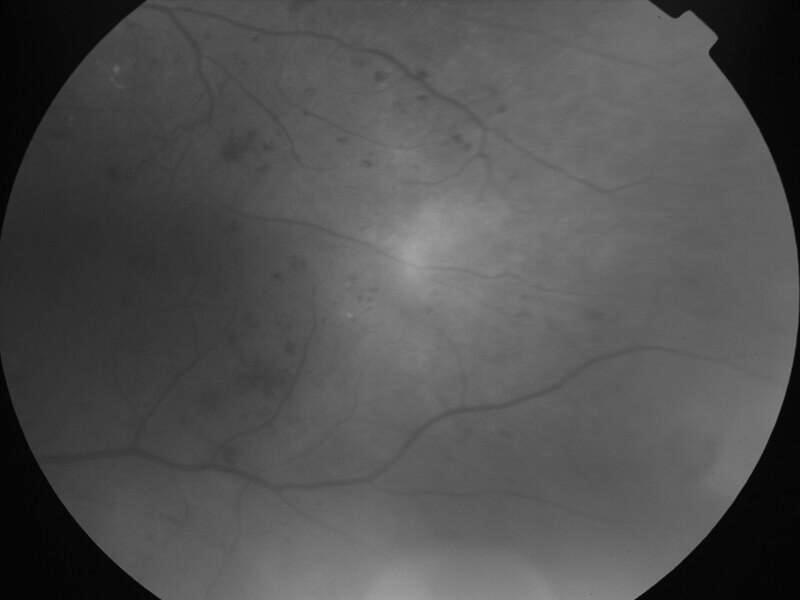

rétinopathie diabétique pré-proliférante